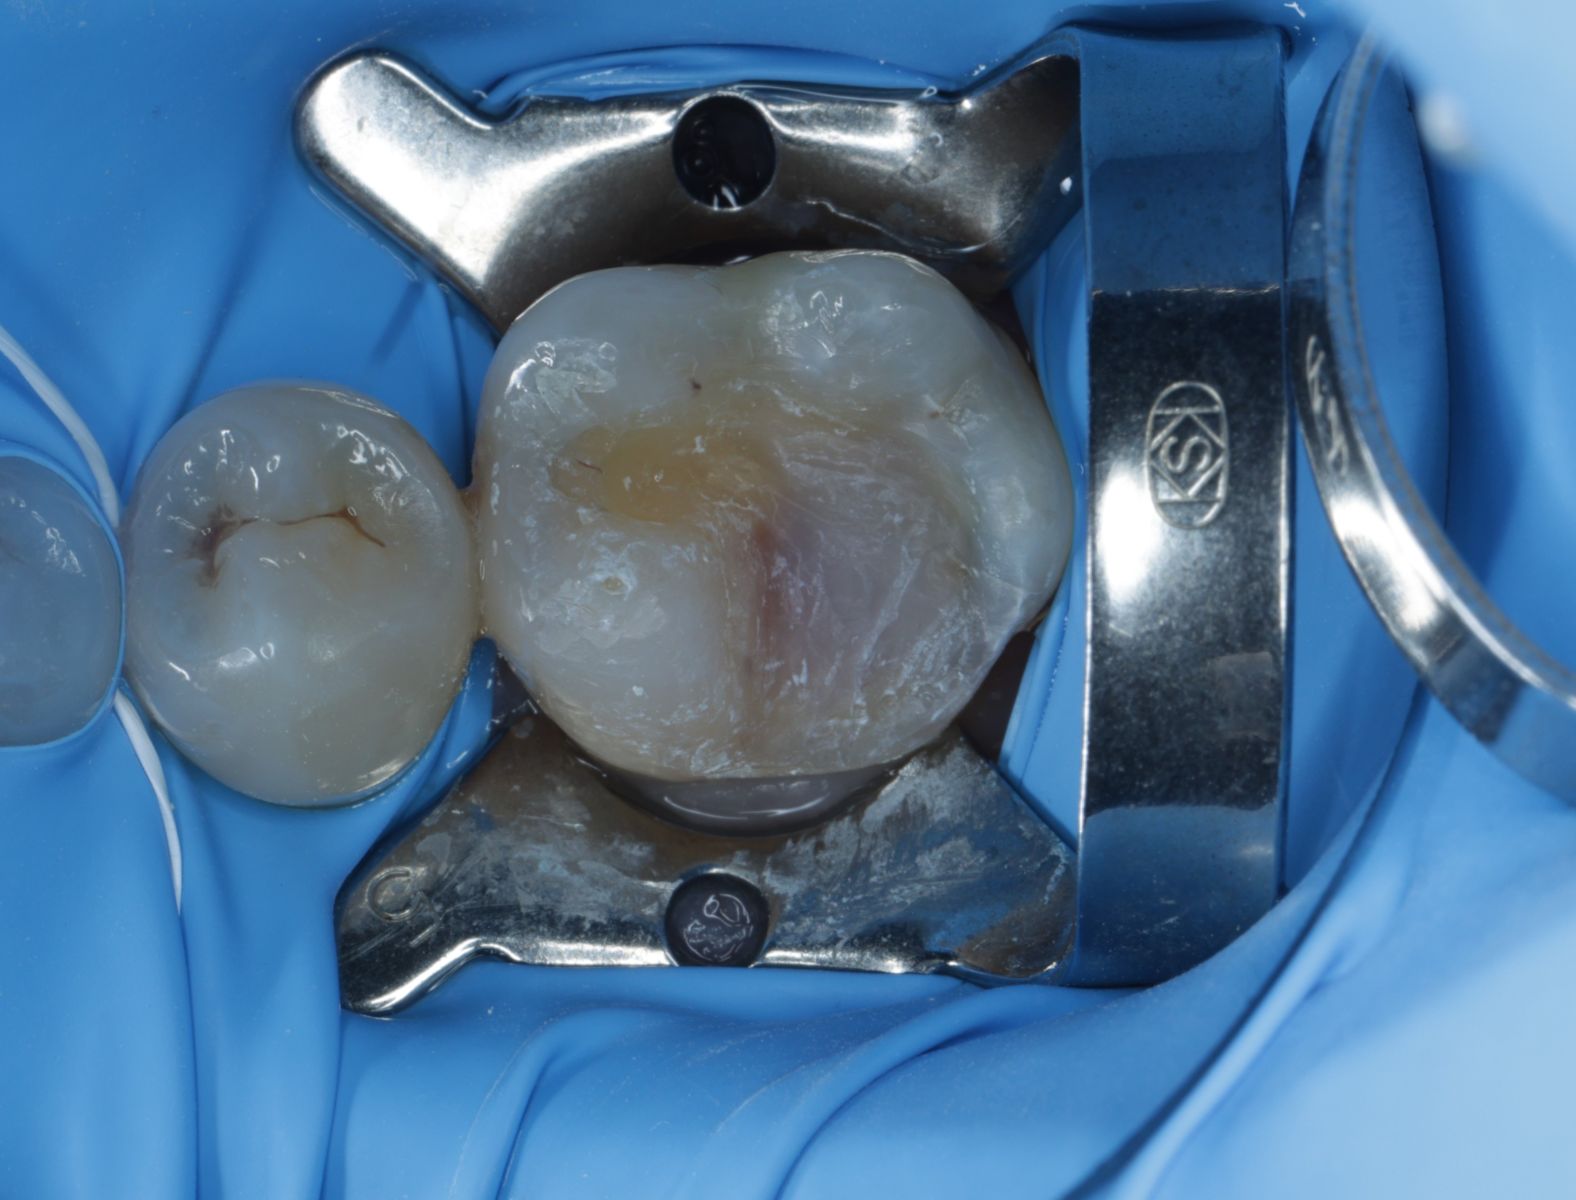

【 案 例 一 】

- 以前大範圍的樹脂補牙,久了造成二次蛀牙,不只是材料不密合,原本的牙齒還可能斷裂。把蛀牙挖乾淨後,隔絕感染源再印模,待陶瓷齒雕送回後再以特殊黏膠黏著完成!經過全陶瓷齒雕修復後,跟原先相比之下,牙齒恢復外型以外還能增強牙齒強度。